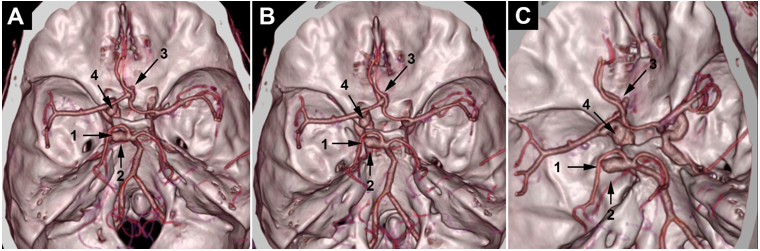

A 43-year-old hypertensive woman visited the emergency department of her local community for a sudden onset of headaches. On the physical exam, she was hemodynamically stable with a blood pressure of 150/90 mm Hg. Her Glasgow Coma Scale (GCS) score was 15/15, and her pupils were isochoric and reactive to light and accommodation. No seizures, visual disturbance, sensorimotor deficit, or fever were noticed. A brain CT showed diffuse SAH with blood in basal cisterns, cerebellar tentorium, and temporal sulci associated with discreet brain edema (Figure 1). The SAH was graded as Hunt and Hess grade 1 and Fisher CT grade 3. Given brain CT results and hypertensive peak, aneurysmal SAH was suspected. Thus, the patient was referred to the neurosurgery department. On admission, her GCS score was 14/15, and she had neck stiffness, photophobia, and phonophobia. In addition, left-sided ptosis and mydriasis were elicited, suggesting left oculomotor nerve palsy. The DSA was unavailable at our institution (a public hospital), and the cost was prohibitive at private facilities. So, a brain CTA with 3D reconstruction was performed, which revealed a 10 mm left paraclinoid aneurysm and a 9 mm left PCA aneurysm (Figure 2, Figure 3, Figure 4). The initial therapeutic strategy was maintaining systolic pressure between 120 and 140 mm Hg using an antihypertensive drug and preventing vasospasm using nimodipine. Since endovascular therapy was unavailable, surgeons chose surgical clipping. Therefore, the patient was transferred to the operating room, placed in the dorsal decubitus position, and the head right turned 60 degrees. Then, a left fronto-temporo-pterional craniotomy was performed. The paraclinoid aneurysm was oriented behind and was wide-necked. Its sac was bilobed and close to the pituitary fossa, the posterior communicating artery (PCOA), the superior wall of the cavernous sinus, and the left clinoid processes. Thus, the operating field was too narrow, and clipping might injure surrounding structures. Therefore, surgeons preferred muscle wrapping instead of clipping. The posterior aneurysm had a wide neck involving the left SCA and PCA origins and was close to the P1 and P2 segments. However, there was a good safety margin to clip the neck without interrupting the blood flow in the SCA and the PCA, which has been done. Despite successful surgery, the patient remained unconscious. On the sixth postoperative day, a brain CT was performed. It revealed a ventricular hemorrhage with diffuse cerebral edema, graded as Hunt and Hess 5 and Fisher CT grade 4. Thus, an external ventricular drain was urgently placed. Unfortunately, the patient succumbed to this event.

Figure 2.Sagittal, axial, and coronal slices of the brain CTA: the paraclinoid aneurysm (1) is close to the left clinoid processes and the left posterior communicating artery (2). The CTA shows a left posterior cerebral artery aneurysm (3). The origin of the left superior cerebellar artery (4) is not visible.

Figure 3.3D CTA images: we can see that the posterior aneurysm involves (1) the left posterior cerebral artery origin, but the origin of the left superior cerebellar artery (2) is still not clear. We can also see the paraclinoid aneurysm (3).

Figure 4.3D CTA volume rendering: the posterior aneurysm (1) involves the left posterior cerebral artery origin. The origin of the superior cerebellar artery (2) is still not clear. A little suspicious outpouching from the anterior communicating artery complex (3) is observed. The paraclinoid aneurysm is indicated in (4).

As a part of our research routine, we realized a retrospective CTA-based 3D modeling using the « 3D slicer » software. The 3D model’s results met the surgical findings concerning the paraclinoid and posterior aneurysm (Figure 5). In addition, it incidentally revealed a 5.2mm ACOA aneurysm (Figure 6). After discussion with neurosurgeons, the rebleeding was attributed to the rupture of the ACOA aneurysm.

In our case, the paraclinoid aneurysm was of the inferior type, according to Krisht and Hsu’s classification. It was wide-necked and close to the left clinoid processes, the left PCOA, and the superior wall of the left cavernous sinus. Given these features, muscle wrapping was the best option. The anatomical relationships were visible in the CTA. However, it was presented in 2D plans and did not give an exact vision of the surgical field. An automatic 3D reconstruction was performed. Compared to the 3D slicer model, its quality was clearly inferior and was presented in 2D flat images. However, the 3D slicer modeling gave a high-quality stereoscopic representation of the surgical anatomy, reproducing the surgical observation. Such a realistic simulation could help surgeons choose the best approach and therapeutic option before surgery. Indeed, if surgeons had the 3D slicer model before the surgery, they would have certainly chosen the wrapping option rather than clipping. The literature reports that 3D slicer modeling results agree with intraoperative conditions. It generates a « déjà vu » feeling that enhances surgical confidence [3].

Posterior cerebral artery aneurysms

PCA aneurysm is rare, with less than 2% incidence. It is often dissecting, has different shapes, rarely saccular. It often involves P1 and P2, rather than P3 and P4 segments. PCA aneurysm surgery is also challenging because of anatomical relationships with surrounding perforators, deep veins, and cranial nerves [4]. In our case, the CTA with 3D mode showed that the posterior aneurysm involved the left PCA. However, 3D slicer modeling showed an SCA aneurysm incorporating the origin of the PCA. The results met surgical findings again. This discordance with the radiologist’s interpretation was related to the 2D aspect of the CTA. Indeed, the original stem of the SCA and the aneurysm overlapped in the three views of the CTA, and the radiologist could not discern the origin of the SCA. Given the small caliber of the left SCA, its origin was not clearly visible in the 3D CTA. In the 3D slicer modeling, the manual drawing allows us to model small-caliber vessels. Then, with the rotation tool, we create an appropriate angle of view to discern the SCA origin. Reviewing the literature, we found only two cases of aneurysms involving SCA and PCA origins reported by Aguilar-Perez et al. and Signorelli et al. In both cases, the aneurysm neck was not clipped but reconstructed by pCONus-assisted coiling [12]. In our case, the aneurysm neck presented a safety margin to isolate SCA and PCA origins from the clipping zone. So, it was possible to clip it.